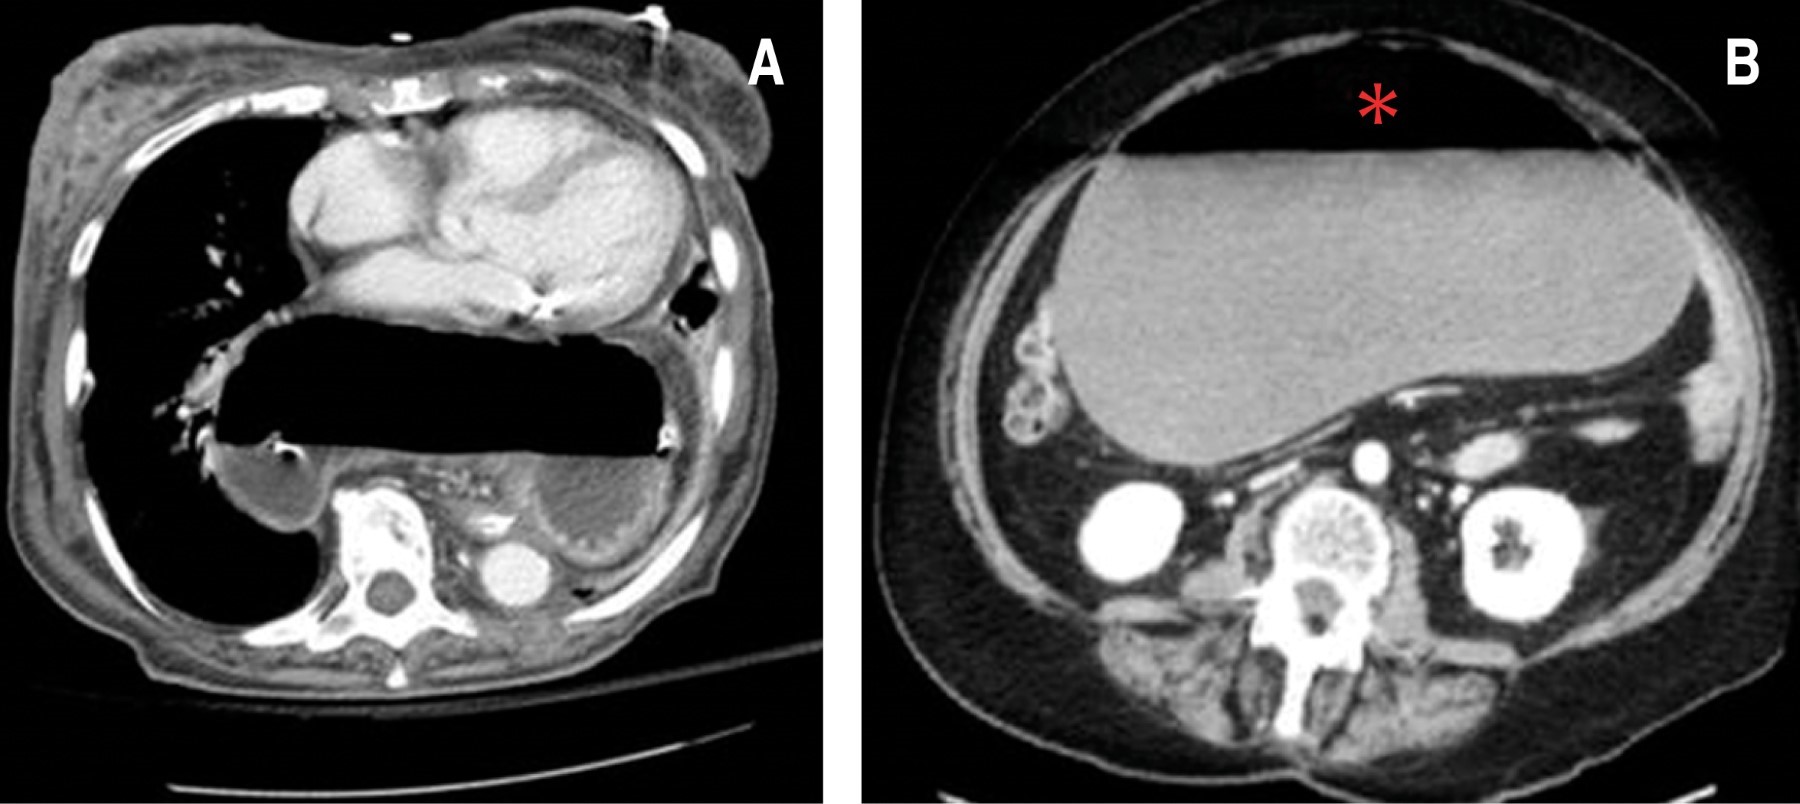

A 50-year-old woman with a history of type 2 diabetes, untreated hypertension, morbid obesity, and hysterectomy 20 years ago was admitted to the hospital. Her condition began three days prior to admission with progressive cramping pain in the epigastrium, abdominal distension, nausea, and vomiting on multiple occasions, dyspnea at rest, non-quantified febrile episodes, and no bowel movements for the last five days. Her vital signs were blood pressure 133/100 mmHg, heart rate 122 beats per minute, respiratory rate 36 breaths per minute, and temperature 37.7 oC. On examination, the left lung fields were hypo ventilated, the rigid abdomen showed generalized distension, tympanic on percussion, and intense pain on palpation predominantly in the epigastrium, no peristalsis was heard, and the rebound sign was positive. Hydric resuscitation was started, and laboratory studies were requested. A computed axial tomography scan showed signs of a hiatal hernia grade IV and toxic megacolon (Figure 1). Laboratory results were as follows: blood white cells of 16,300 cells/µl, neutrophil count of 14,000 cells/µl, hemoglobin 17.3 g/dl, platelet count of 409,000 u/µl, arterial blood gas with lactate 5.5 mmol/l and pH 7.48. Gastric decompression was performed via a nasogastric tube (NGT) placed without difficulty. Ranitidine 50 mg iv, dexamethasone 8 mg iv, metoclopramide 10 mg iv, ceftriaxone 1 g iv, butylhioscin 20 mg iv, and paracetamol 1 g iv were administered. An exploratory laparotomy was performed on 12/07/18 and a grade IV hiatal hernia was found with a secondary gastric volvulus type II showing gastric necrosis. Reduction of the hernial sac and of the GV, a Nissen type fundoplication and a partial gastrectomy with Billroth II technique in manual Brown's omega were performed. Closure as done with Prolene intestinal needle 3-0 in two planes with Connell and Mayo stitches, as well as a Lembert reinforcement and esophageal hiatus plasty with Prolene® intestinal needle 2-0 simple stitches. No complications occurred at that time; an antibiotic regimen of ciprofloxacin 400 mg iv, every 12 hours for 10 days and metronidazole 500 mg iv, every eight hours for 10 days was indicated, and she was admitted into the Intensive Care Unit. One week later, she presented a 50% dehiscence of the gastro-jejunal anastomosis, with leakage of gastric contents. Primary gastric closure was performed with a Graham patch, and a Bogota bag was placed. Her postoperative lab results showed a leukocytosis of 22,000 cells/µl, neutrophil count of 18,000 cells/µl, hemoglobin level of 8 mg/dl, a platelet count of 123,000 u/µl, pH of 7.31, lactate of 3.9 mmol/l, and data of renal failure associated with creatinine of 3.2 mg/dl, urea of 65 mg/dl, urea nitrogen 45 mg/dl, sodium 153 mEq/l, potassium 2.8 mEq/l, chlorine 110 mEq/l. Later, and due to the persistence of the leak, a surgical cleaning procedure and a partial gastrectomy and Roux-en-Y gastro-jejunal anastomosis in two planes with Connell and Mayo stitches and reinforcement of Lembert stitches with 3-0 Prolene® intestinal needle, and a subsequent jejunostomy using 2-0 silk with simple stitches to abdominal wall aponeurosis were performed. In the following weeks she underwent four surgical cleaning procedures, replacement of the Bogota bag and a Stamm type gastrostomy due to intestinal leakage. She persisted with abdominal sepsis, had a perforation of the anastomosis and a gastric T-tube was placed. In the cavity was found abundant purulent and foul-smelling material, in addition to a frozen abdomen. During her stay she was managed with multiple antibiotic therapy with ciprofloxacin and metronidazole, changing to meropenem 500 mg iv, every eight hours, and subsequent adjustment to tigecycline 100 mg iv, continuing with 50 mg iv, every 12 hours and vancomycin 1 g iv, every 12 hours for 10 days, in addition to total parental nutrition, showing no improvement in her general status. Due to positive peritoneal fluid cultures for multi-resistant Staphylococcus aureus and Acinetobacter baumannii, her morbid obesity and poor nutritional status, she developed septic shock of abdominal focus, and died one month after admission.

Its clinical presentation varies according to etiology, speed of progression, type of volvulus, degree of rotation and resulting obstruction, so the symptoms may mimic any abdominal condition. In the acute form, Borchardt's triad (severe epigastric distention with abdominal pain, intractable retching, and inability to pass a gastric tube) is diagnostic in 70% of adult patients.3,10 The subacute form of gastric volvulus is characterized by vague abdominal discomfort, while in chronic GV the symptomatology is nonspecific with epigastric pain, early satiety, nausea or vomiting.8 Other symptoms may be atypical chest pain, anemia, weight loss, dyspnea, reflux, postprandial abdominal distention. or dysphagia and may appear irregularly over weeks or years.7 The high probability of exacerbation of chronic VG should be reminded. Secondary complications of acute GV are gastric ileus, pyloric ischemia, gastric necrosis with perforation, and even death.3,11 Diagnosis is usually difficult due to a low clinical suspicion and can range from being an incidental radiological finding to an urgent situation.12 Abdominal plain X-rays usually show gastric dilatation with gas scarcity in the remaining part of the intestine.2 If the GV is secondary to a diaphragmatic defect, a retrocardiac air bubble or air level may be found in the chest (Figure 3); especially in the mesenteric-axial form the gastric shadow shows a double level of air and fluid in the standing position, while in the organ-axial form, the stomach is more horizontally positioned with a single fluid level.13 An upper gastrointestinal barium series is considered more specific than the plain radiographs, as it reveals the obstruction of the stomach at the site of the volvulus and its distension at the level of the diaphragm (Figure 4).8 In our case, the presentation was not the classic one, and therefore an accurate preoperative diagnosis was not achieved. It was necessary to perform a CT scan, which is consistent with the study by Mazaheri et al, which supports its use since this imaging study has the highest sensitivity and specificity for the diagnosis of GV and an accuracy of 90%. In the CT scan imaging, the most important finding is the transition point of the pyloric peak,14 which confirms the diagnosis with anatomical details and possible associated conditions (paraesophageal and diaphragmatic hernias, diaphragmatic eventration). In a late stage of a GV, the vascular involvement may result in findings of gastric ischemia, ulceration, or gastric mucosal fissures.11,15 The hemodynamic status of our patient did not allow further studies to be performed so we proceeded to perform an urgent exploratory laparotomy. Treatment can be conservative or surgical depending on the clinical presentation and possible associated anomalies. While in the acute phase the GV should be treated with an emergency surgical intervention, there are no clear guidelines on the management of chronic GV.11,14 Initial management should be with a gastric tube placement for decompression, followed by surgery to check gastric viability, resection if necrosis is present, and a definitive surgical treatment such as reduction of rotation, gastrostomy, gastropexy, and repair of predisposing defects.17 In a retrospective study of patients with GV and conservative management for five years, it was found that symptomatic recurrence was 64%, but this is only an option for patients with chronic GV, especially those over 60 years of age and with high surgical risk17 and involves reduction or percutaneous endoscopic gastrostomy plus prokinetic and antisecretory treatment. However, there is a high risk of gastric perforation.16 In our case it was determined that the patient was not a candidate for this type of management.1,18 Minimally invasive surgery, such as endoscopic de-rotation and single incision laparoscopic surgery, has gained ground over classic techniques due to the lower rate of complications, with less bleeding and shorter hospital stay, so it is necessary to establish a standard procedure under this technique. The option of a more drastic management with the performance of a total gastrectomy with end-to-end esophageal-jejunal anastomosis should be considered from the beginning, trying to avoid complications, the risk of infection and repetitive surgical trauma.12

Figure 1